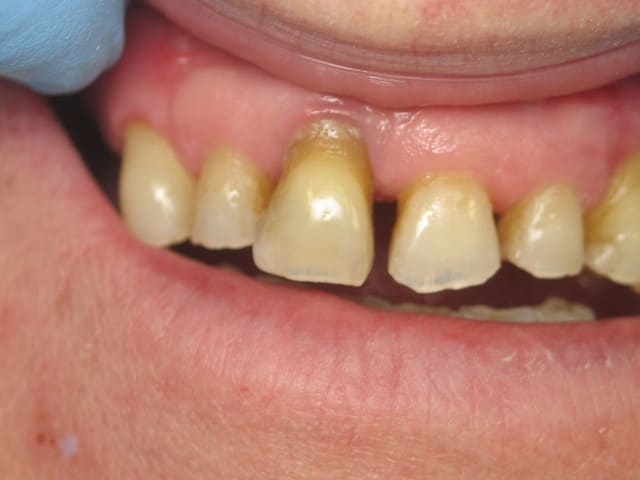

je refait actuellement les 4 incisives, le projet initial consistait à faire 4 dents

j'ai été un peu présomptueux sur mes capacités à conserver 11,

je doit me résoudre à l'extraire,

j’envisage de faire un bridge céramo céramique,

A priori pas de calage postérieur (cf. photo)?

Ton bridge CCC il va te l’exploser..... Déjà un bridge CCM je serai pas très confiant.

avec si peu de dents derrière (pas du tout ??)

je vois pas quel pronostic tu peux espérer pour le bridge

Présenté comme cela, évidement une réhabilitation uniquement antérieure fixé semble vouée à l'échec.

La perte paro importante sur 11, l'égression des 11 et 21 avec diastème et l'usure importante montrent un manque de calage postérieur existant depuis un bon moment (présence certaine d'une PAP maxillaire, non adaptée, non rebasée). Il n'y a pas de raison que tout cela s'arrange juste en refaisant les incisives sup.

Une réhabilitation totale semble plus indiquée (prothèse mixte conjointe/adjointe, ou mieux implanto portée).

Pour la ligne du sourire, difficile de dire si cela aura un impact (pas de photo de sourire disponible), mais vu la perte osseuse visible sur la rétro, il y a fort à parier que tu vas te retrouver avec une belle fonte de la corticale vestibulaire quelques mois après extraction: comblement bio-oss possible+travail de l'esthétique de l'émergence du pontique.